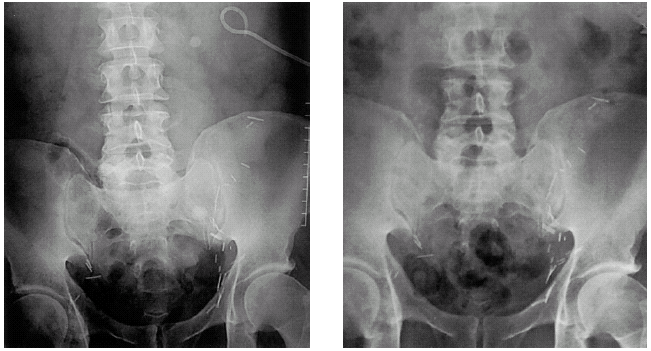

Extrofia vesical es una malformación congénita del aparato urogenital, en donde la mucosa de la vejiga se encuentra al descubierto y se aprecian con facilidad uréteres y uretra. Esta malformación ocurre tanto en bebés recién nacidos como en animales.

El diagnóstico incluye anomalías en la pared abdominal inferior, vejiga, pelvis ósea, y los genitales externos.